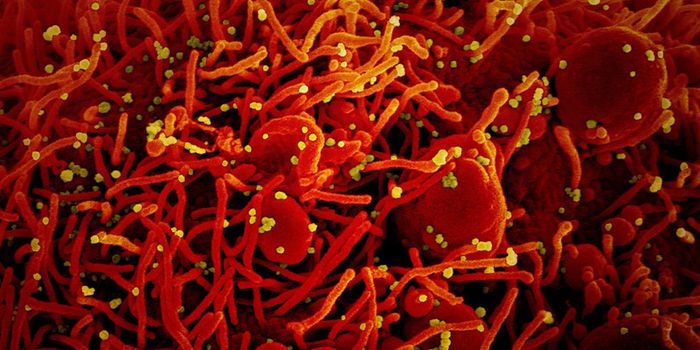

JUL 05, 2020Cell & Molecular BiologyThe pandemic virus SARS-CoV-2 enters the body through the respiratory system to cause the illness COVID-19. But we know ...